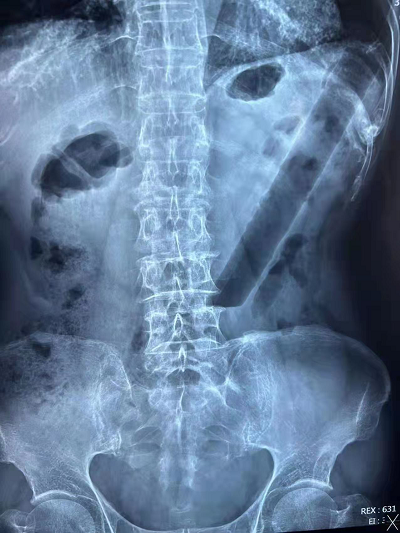

3月19日下午臨近下班,肛腸二科門診趙金龍醫(yī)生接診了一名85歲高齡的特殊患者,患者在外院行腹部平片,示結(jié)腸異物。經(jīng)過詳細(xì)詢問病史后得知患者兩天前因排便不暢,自行用一根直徑約3cm,長約20cm的空心硬塑料管協(xié)助通便,結(jié)果無法自行取出。隨著時間的推移,塑料管的位置也越來越深,患者下腹部也開始脹痛不適,輾轉(zhuǎn)市內(nèi)其他醫(yī)院后來到我院肛腸二科門診就診。

趙醫(yī)生在向韓義民主任匯報患者病情后將患者收住入院,完善相關(guān)檢查后緊急在結(jié)腸鏡下行“經(jīng)內(nèi)鏡異物取出術(shù)”。結(jié)腸鏡顯示異物嵌頓于乙狀結(jié)腸距肛門口約25cm的位置,直腸和乙狀結(jié)腸多發(fā)片狀潰瘍。因為異物為比較銳利的斜切口,所以取出時一不小心就會劃破腸道黏膜,甚至?xí)斐赡c穿孔,所以整個操作過程需要高度的警惕和完美的配合。在繆磊、趙金龍、張祚綸三位醫(yī)生和譚曉霞護(hù)士相互配合下,沿著腸道的走形方向緩慢退鏡,直至將異物拖至直腸,然后借助器械和外力的作用將異物擠壓變形,最后將異物拖出直腸,整個手術(shù)過程歷時1個小時。術(shù)后給予消炎等支持對癥治療,患者于3月23日痊愈出院。